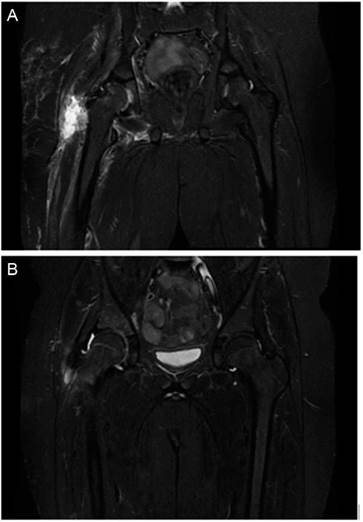

El segundo día de ingreso se hace resonancia magnética, (RM) en la que se objetiva osteomielitis en acetábulo y miositis del músculo obturador externo y de los músculos aductores (fig. 1).

Figura 1 A) Osteomielitis acetabular y miositis del músculo obturador externo y de los músculos aductores. B) Mejoría significativa del edema óseo acetabular. Importante disminución del edema muscular.

La PCR para Kingella kingae en líquido articular es negativa y en los cultivos del mismo no se detecta crecimiento hasta el séptimo día, en el que avisan por aislamiento de Fusobacterium nucleatum, por lo que se cambia el tratamiento a ampicilina y metronidazol intravenosos en espera del antibiograma. Tras comprobar sensibilidad, se modifica a clindamicina intravenosa; sin embargo, tras la aparición de exantema compatible con toxicodermia (impresiona secundario a administración de clindamicina) se vuelve a cambiar la antibioterapia a metronidazol intravenoso. A partir de este cambio se presenta evolución favorable, con mejoría de la movilidad y normalización de los reactantes de fase aguda; además, se comprueba mejoría en la RM (fig. 1).